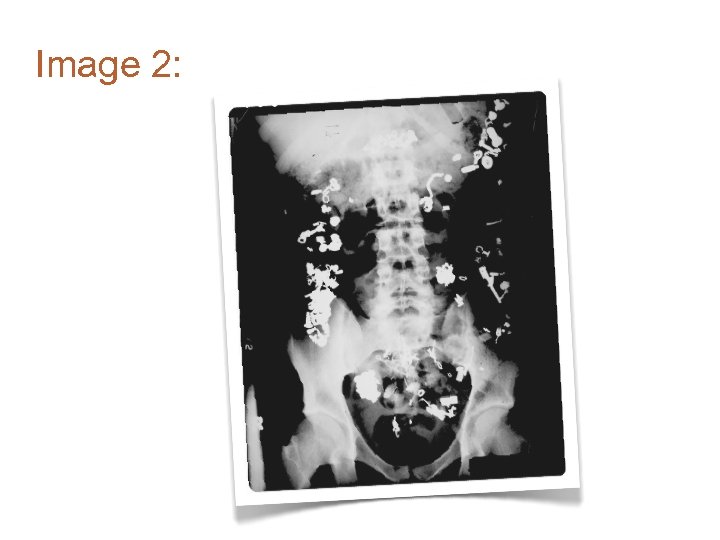

Image 3: